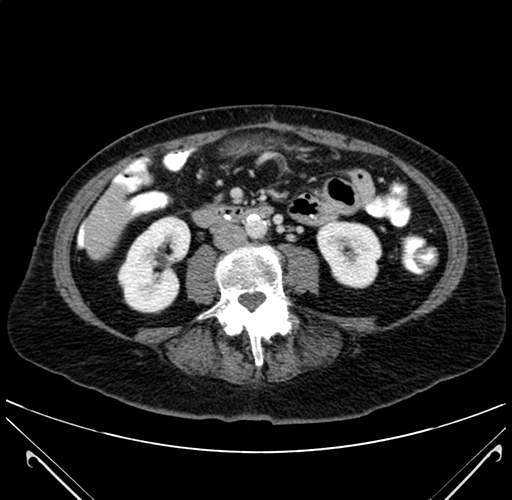

Pre-Chemo: Axial Venous